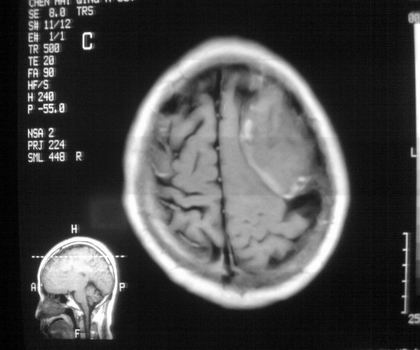

以下是引用影像孺子牛在2008-4-29 21:20:00的发言:[br]首先病变定位在脑外,根据ct密度及mri信号特征考虑慢性硬膜下血肿不连续环形钙化。

以下是引用周战梅在2008-4-29 23:12:00的发言:[br]脑外病变,蛛网膜下腔增宽,囊壁点状、环形钙化,增强扫描呈不均匀环状强化,考虑为囊性脑膜瘤可能性大,慢性脓肿、血肿机化、胆脂瘤不能除外。